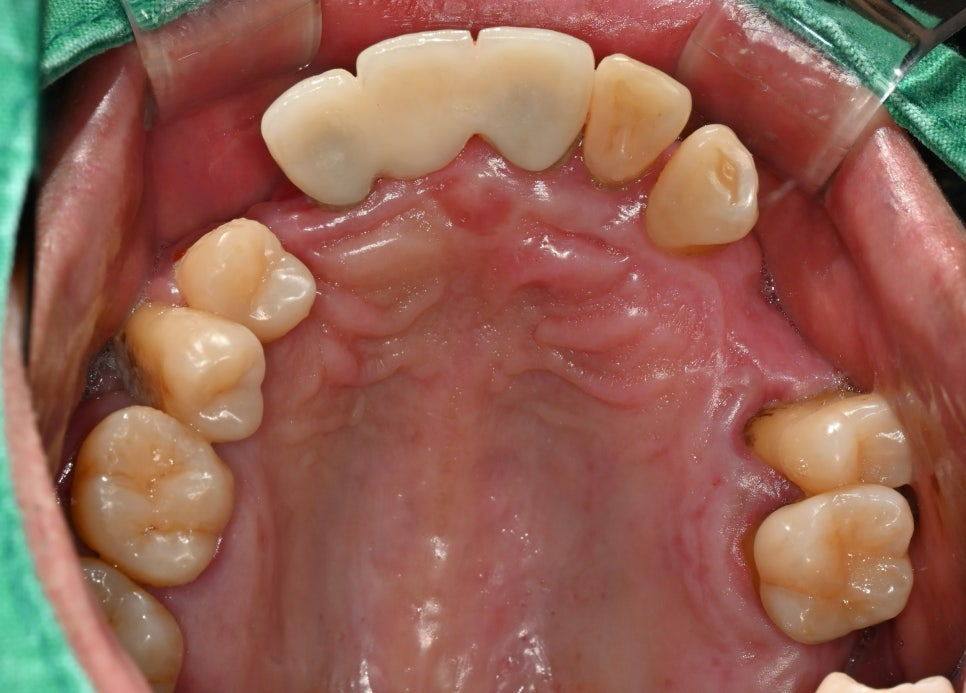

상악은 기성 어버트먼트를

장착하였으며

하악은 임시 치아를

제작하여 체결했습니다.

이렇게 위아래 다른 이유는,

2024.09.20

윗쪽는 전체 틀니를 사용해도

불편감이 크지 않은 반면

그에 반하여 아래는

의치가 오히려 더 힘들 수 있어

임시 보철을 체결한 것 입니다.

상악은 골 흡수가 많아

안정적으로 유착되려먼

하중을 부여하지 않는 것이

더욱 유리합니다.

그러므로 틀니가 더욱 적합했죠.

반대로 하악은 즉시 하중을

부하하더라도

치유 과정에 영향이 없어

임시로 치아를 올릴 수 있었습니다.

보시면 잇몸 쪽으로 실밥이

튀어나와있습니다.

술 후 바로 체결하였기 때문입니다.